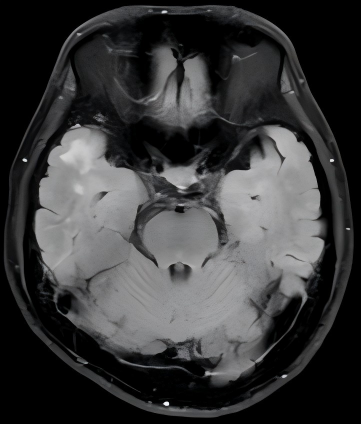

神经内科二科的医生接诊了他。通过详细的问诊和查体,查阅既往资料,医生第一时间为他安排了头颅磁共振复查。影像结果确实显示小杨大脑双侧颞叶存在异常信号,与放射性脑病的影像改变高度相似。

为验证判断,医生迅速为小杨安排了肌电图、眼科会诊、基因检测等系列检查。最终,肌电图提示"肌强直放电",基因检测显示DMPK基因的一个等位基因CTG拷贝数达150次(正常值<50)。基于此,小杨被明确诊断为强直性肌营养不良1型。